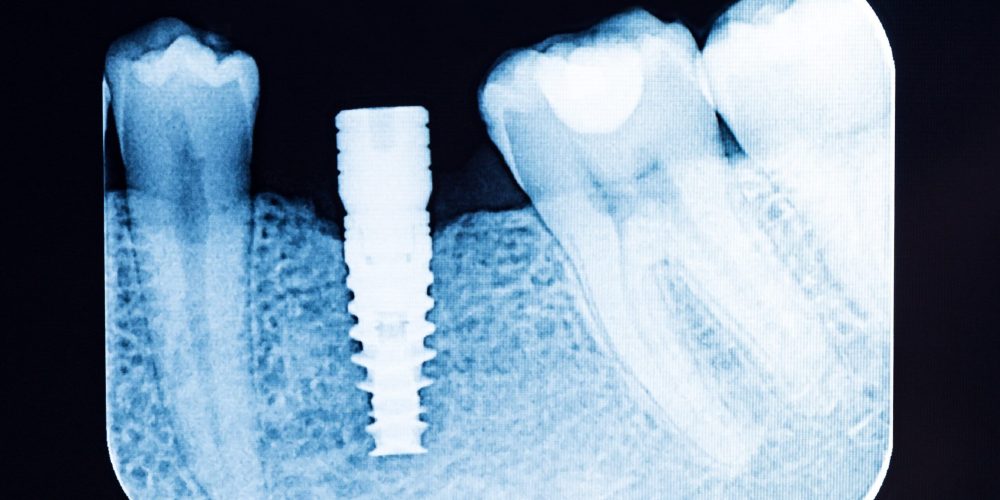

A dental implant is a small titanium post that acts as a missing tooth’s root. After being surgically placed into the jawbone, it fuses with the bone. This process is called osseointegration, that creates a strong, stable foundation. Once the implant is secure, a custom-made crown is attached that looks, feels, and functions just like a natural tooth.

- Placing the Implant: The titanium implant is gently placed into your jawbone during a minor surgical procedure.

- Healing and Integration: A solid foundation is created as your jawbone naturally fuses with the implant over the next few months.